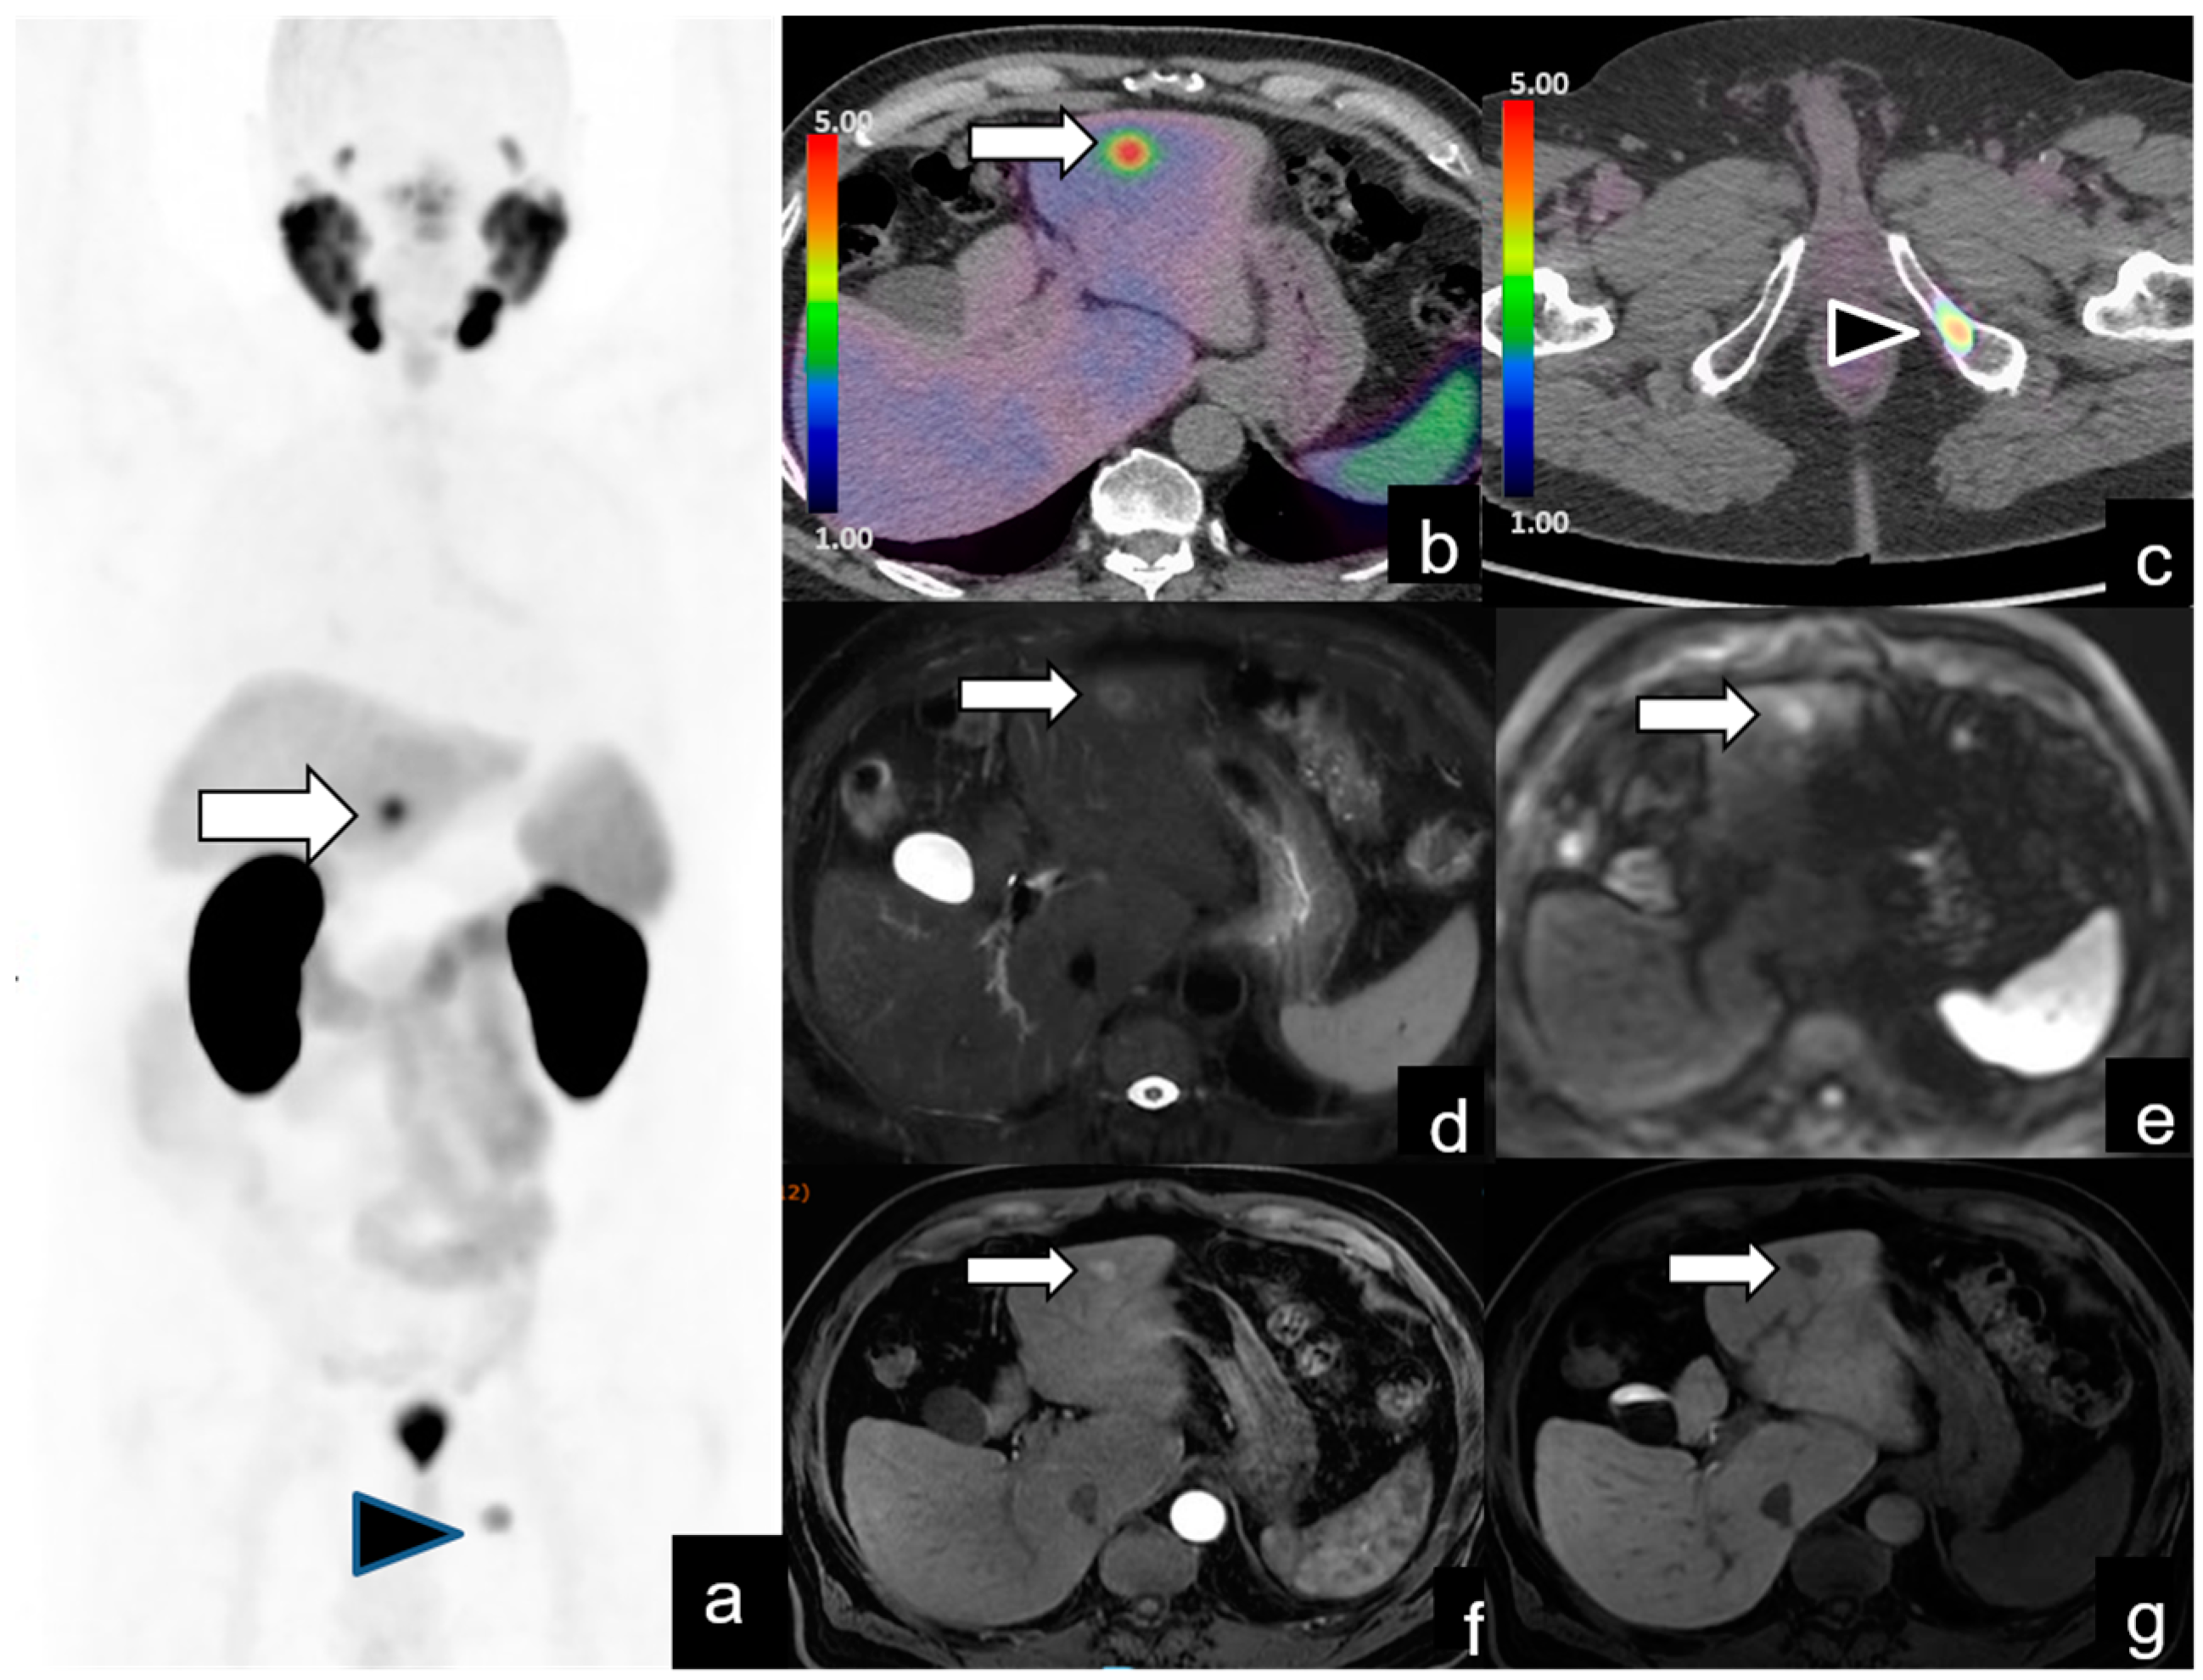

| Bone metastases | 20/128 (15%) | 19 | 1.9–70 | ||

| Other (e.g., lung, liver) metastases | 5/128 (3%) | 14.6 | 2.5–17 |